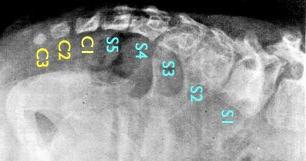

Onderstaande figuur is een röntgenfoto van een zesjarig meisje met een staart. De vijf sacrale wervels (wervels van het heiligbeen) en de drie coccygale wervels (die van het staartbeen) zijn genummerd. Het gehele os coccygis is normaal even groot als de vijfde sacrale wervel. Hierbij is het os coccygis dus drie keer zo groot als normaal. In dezelfde studie als waaruit deze foto komt, hebben de chirurgen twee andere gevallen met een echte staart gerapporteerd, waarvan één met drie staartwervels en één met vijf(6).

Figuur 4.

Een röntgenfoto van een menselijke staart.